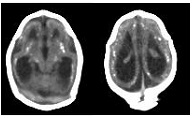

zika brain scansBOSTON – In a special report released August 23 in the journal Radiology, a team of researchers including Deborah Levine, MD, Director of Obstetric & Gynecologic ultrasound at Beth Israel Deaconess Medical Center (BIDMC) and professor of radiology at Harvard Medical School (HMS), documented the brain abnormalities associated with congenital Zika in 45 confirmed and presumed cases from northeastern Brazil. Today, more than 50 countries and territories report the active transmission of Zika virus, a mosquito-borne illness linked to microcephaly in babies born to infected mothers. The current Zika outbreak began more than a year ago in Brazil, where there have been more than 8,300 reports of microcephaly.

The most common trait across all 45 patients was a reduction in brain tissue volume, visible in every subject. Among the other common traits, the radiologists saw enlarged fluid-filled ventricles in 16 of the 17 babies with confirmed congenital Zika infection and 27 out of 28 of those with presumed infections. Notably, three fetuses with normal head circumference demonstrated severe enlargement of the ventricles, an abnormality linked to developmental delays.

Images also revealed calcium build-up in 100 percent of the patients. Calcification occurred in several regions of the brain, especially at the junction of the gray matter and white matter, a location not typically seen in other congenital infections. The scans also revealed calcification in the thalamus (a sensory processing organ that coordinates body movement), basil ganglia (a crucial group of neurons at the base of the thalamus) and the brainstem (the central trunk of the brain that links it to the spinal cord).

Patients also exhibited abnormal development of the cortex, the wrinkly outer layer of the brain thought to play a role in consciousness. Though there was substantial variation in the type, region and severity of these abnormalities, in general, the folds on the surface of the brain were either smoothed out or too prominent. These findings, called lissencephaly and polymicrogyria, are linked to viral infections during pregnancy and can often be associated with severe developmental delays and seizures.